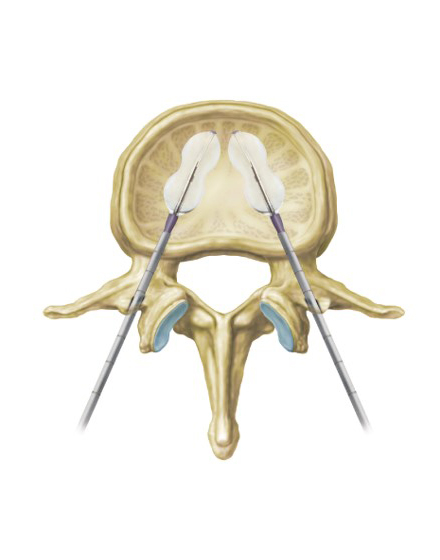

低侵襲脊椎側方固定術 XLIF (エックスリフ)、OLIF(オーリフ)

適応となる疾患:腰椎椎間板ヘルニア、腰部脊柱管狭窄症、腰椎変性すべり症、腰椎変性側弯症など

日本では2013年から承認されている低侵襲な脊椎側方固定術です。この手術は、トレーニングを受けた医師だけが実施できるため、全国でも限られた医療機関でのみ受けられます。当センターの日方医師は資格を有しているため実施可能です。この手術の最大の利点は脊髄神経を直接触らないで神経を圧迫から解除することにあります。側腹部に約5cmの皮膚切開により、下図のように神経機能を電気モニタリングで随時確認し重要な神経を避けながら椎間板内に人工骨を移植します。その後、腰部から固定術を行います。翌日から起立・歩行が許可され、入院期間は通常10~14日程度になります。